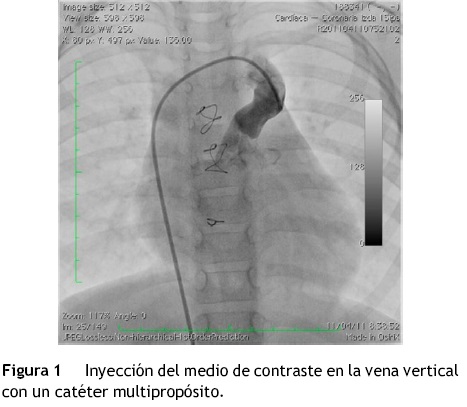

Se realizó el procedimiento avanzando una guía Amplatz extra stiff (Cook Medical, EE. UU.) a través de la vena cava inferior, aurícula derecha, vena cava superior, vena braquicefálica, vena vertical, aurícula izquierda y vena pulmonar superior izquierda. Se hizo oclusión con balón a nivel de la vena vertical y se realizó una inyección selectiva en la rama izquierda de la arteria pulmonar, observando en la levofase un adecuado retorno de las venas pulmonares a la aurícula izquierda (fig. 2A y B). Sobre la guía se avanzó un sistema de liberación de Amplatzer® 8 Fy a través de este se depositó un AVP de 16 mm en la vena vertical para su oclusión. Durante el procedimiento se administraron 50 U/kg de heparina.